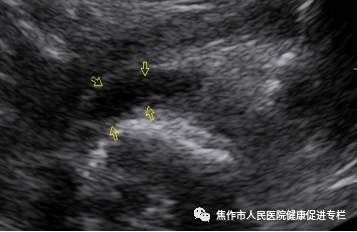

图4:左侧髋关节囊内股骨颈处探及液性回声(黄色箭头)

绝大多数患儿表现为除关节囊增厚外,主要表现关节囊内积液,少数可伴滑膜增生。